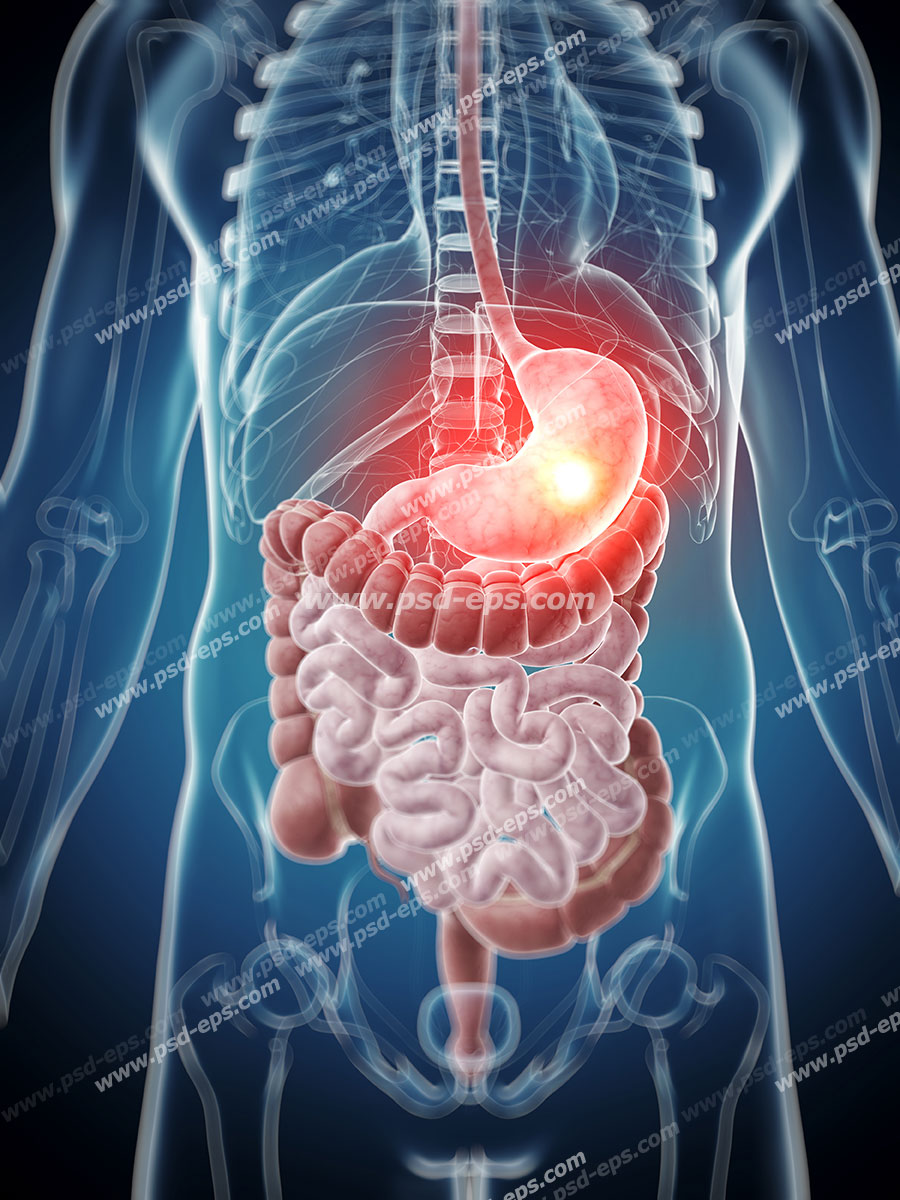

اسکلت داربست بدن است تمام قسمت های بدن روی اسکلت قرارگرفته اند بدن انسان از ۲۰۶ قطعه استخوان تشکیل شده است این استخوان ها طوری با نظم کنار هم قرار گرفته اند که انسان را قادر می سازد حرکات دقیقی داشته باشد. استخوان یک نسج بسیار محکم است زیرا در ترکیب آن منرالها مانند کلسیم و دیگر وجود. اسکلت داربست بدن است تمام قسمت های بدن روی اسکلت قرارگرفته اند بدن انسان از ۲۰۶ قطعه استخوان تشکیل شده است این استخوان ها طوری با نظم کنار هم قرار گرفته اند که انسان را قادر می سازد حرکات دقیقی داشته باشد. آناتومی سه بعدی بدن انسان عکس گرافی بدن امعاء و احشاء بدن آناتومی سه بعدی بدن انسان عکس گرافی بدن امعاء و احشاء بدن قلب کبد روده.